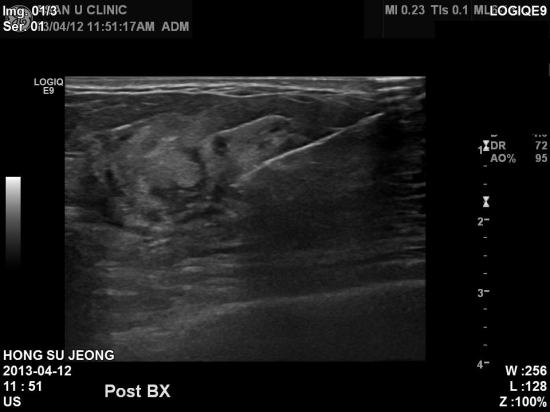

상기환자 2년전 겨드랑이쪽 찌릿찌릿한 통증있으셨고.

유방초음파상 이상소견으로 내원하신 44세 여성분이십니다.

상피내암은 0기암이라 할만큼 병기가 좋아 99%이상의 완치율을 보입니다.

유방암이 세포안에만 국한되어있는 상태라고 할 수

있습니다.